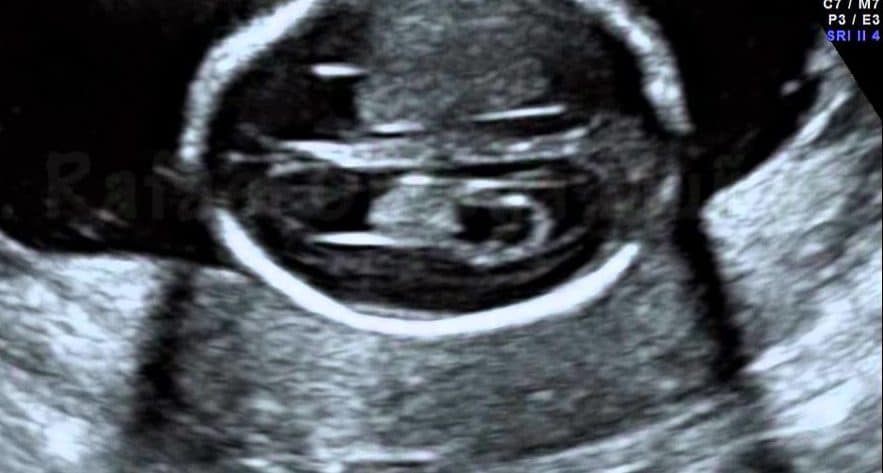

Ultrassom Cisto de Aracnóide

Cisto de Aracnóide

Vídeo cortesia do Dr. Jader Cruz - The Fetal Medicine Foundation Cisto de Aracnóide Os cistos aracnoides são lesões congênitas da membrana aracnoide que…